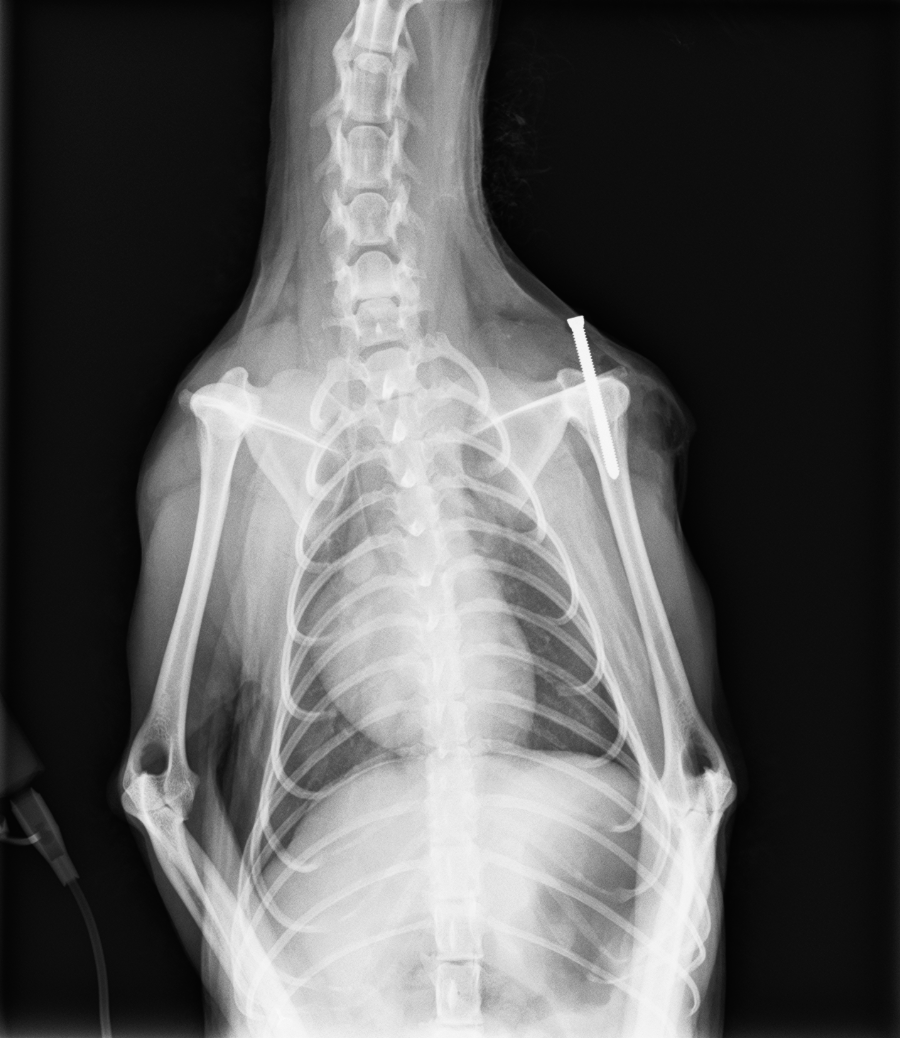

レントゲン検査より、右肩関節脱臼

診断と治療

右肩関節脱臼と診断し、スクリューを上腕骨に挿入し、肩関節を安定化させる

before